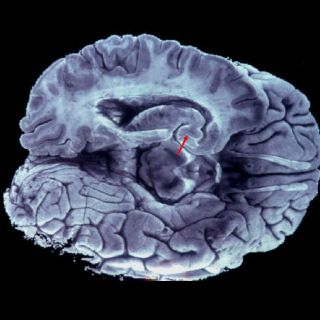

LONDRES, INGLATERRA (01/feb/2016).- Un equipo de científicos de Francia ha creado una réplica en 3D del

cerebro humano con todos sus pliegues y cavidades, lo que contribuirá al estudio de los trastornos de este órgano y su funcionamiento interno, publica este lunes la revista "Nature Physics".

En la revista, los investigadores detallan cómo crearon la estructura, elaborada con un gel elastómero rosa pálido, basándose en imágenes de cerebros de fetos humanos.

Ayudados por investigadores de la Universidad de Harvard (Estados Unidos), los científicos señalan que lograron un modelo que supera las expectativas, pues los pliegues de gel son similares en tamaño, forma y orientación a los que se pueden ver en los cerebros de embriones.

Si bien las dobleces más pequeñas no se encuentran en esta estructura 3D, el modelo se puede reproducir para profundizar en investigaciones al presentar una escala y curvatura casi idéntica a la de un cerebro real.